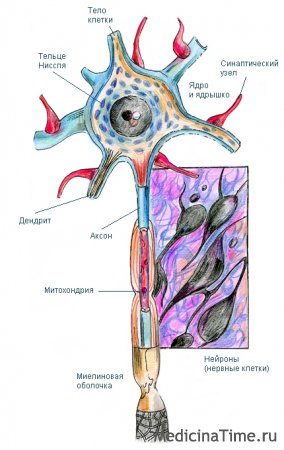

Мир нейроцитов: исследование нервных клеток